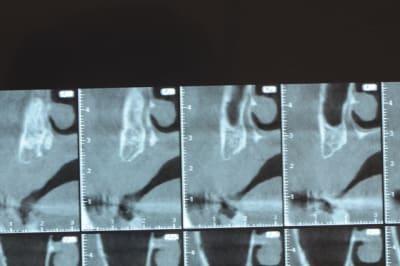

un cas pour PXAV.

j'ai besoin de 4 implants au maxillaire pour faire tenir son complet.

dans la zone postérieur, pas de problème, mais devant, c'est une autre histoire.

avant de faire la tomosynthèse je comprenais pas pourquoi j'avais aussi peu de contraste.

Ce n'est pas vraiment un consensus mais plutot du bon sens. Si tu as une crête en profil de lame de couteau cela signifie que tu as une fusion des corticales vestibulaire et palatine et donc absence de spongieux, ce qui comme tu le sais n'est pas indiqué en implanto (cj os de marbre par exemple)

Il me semble que Palti ou encore Szmukler-Moncler recommandent un minimum de 2-3mm. Si c'est plus fin, greffe d'apposition et GBR.

Dans ton cas il te faudrait abaisser la crête de 3 bons mm pour arriver à cette épaisseur.

Une petite étude de ton cas D57

Les zones exploitables radiologiquement parlant:

Coupes implant